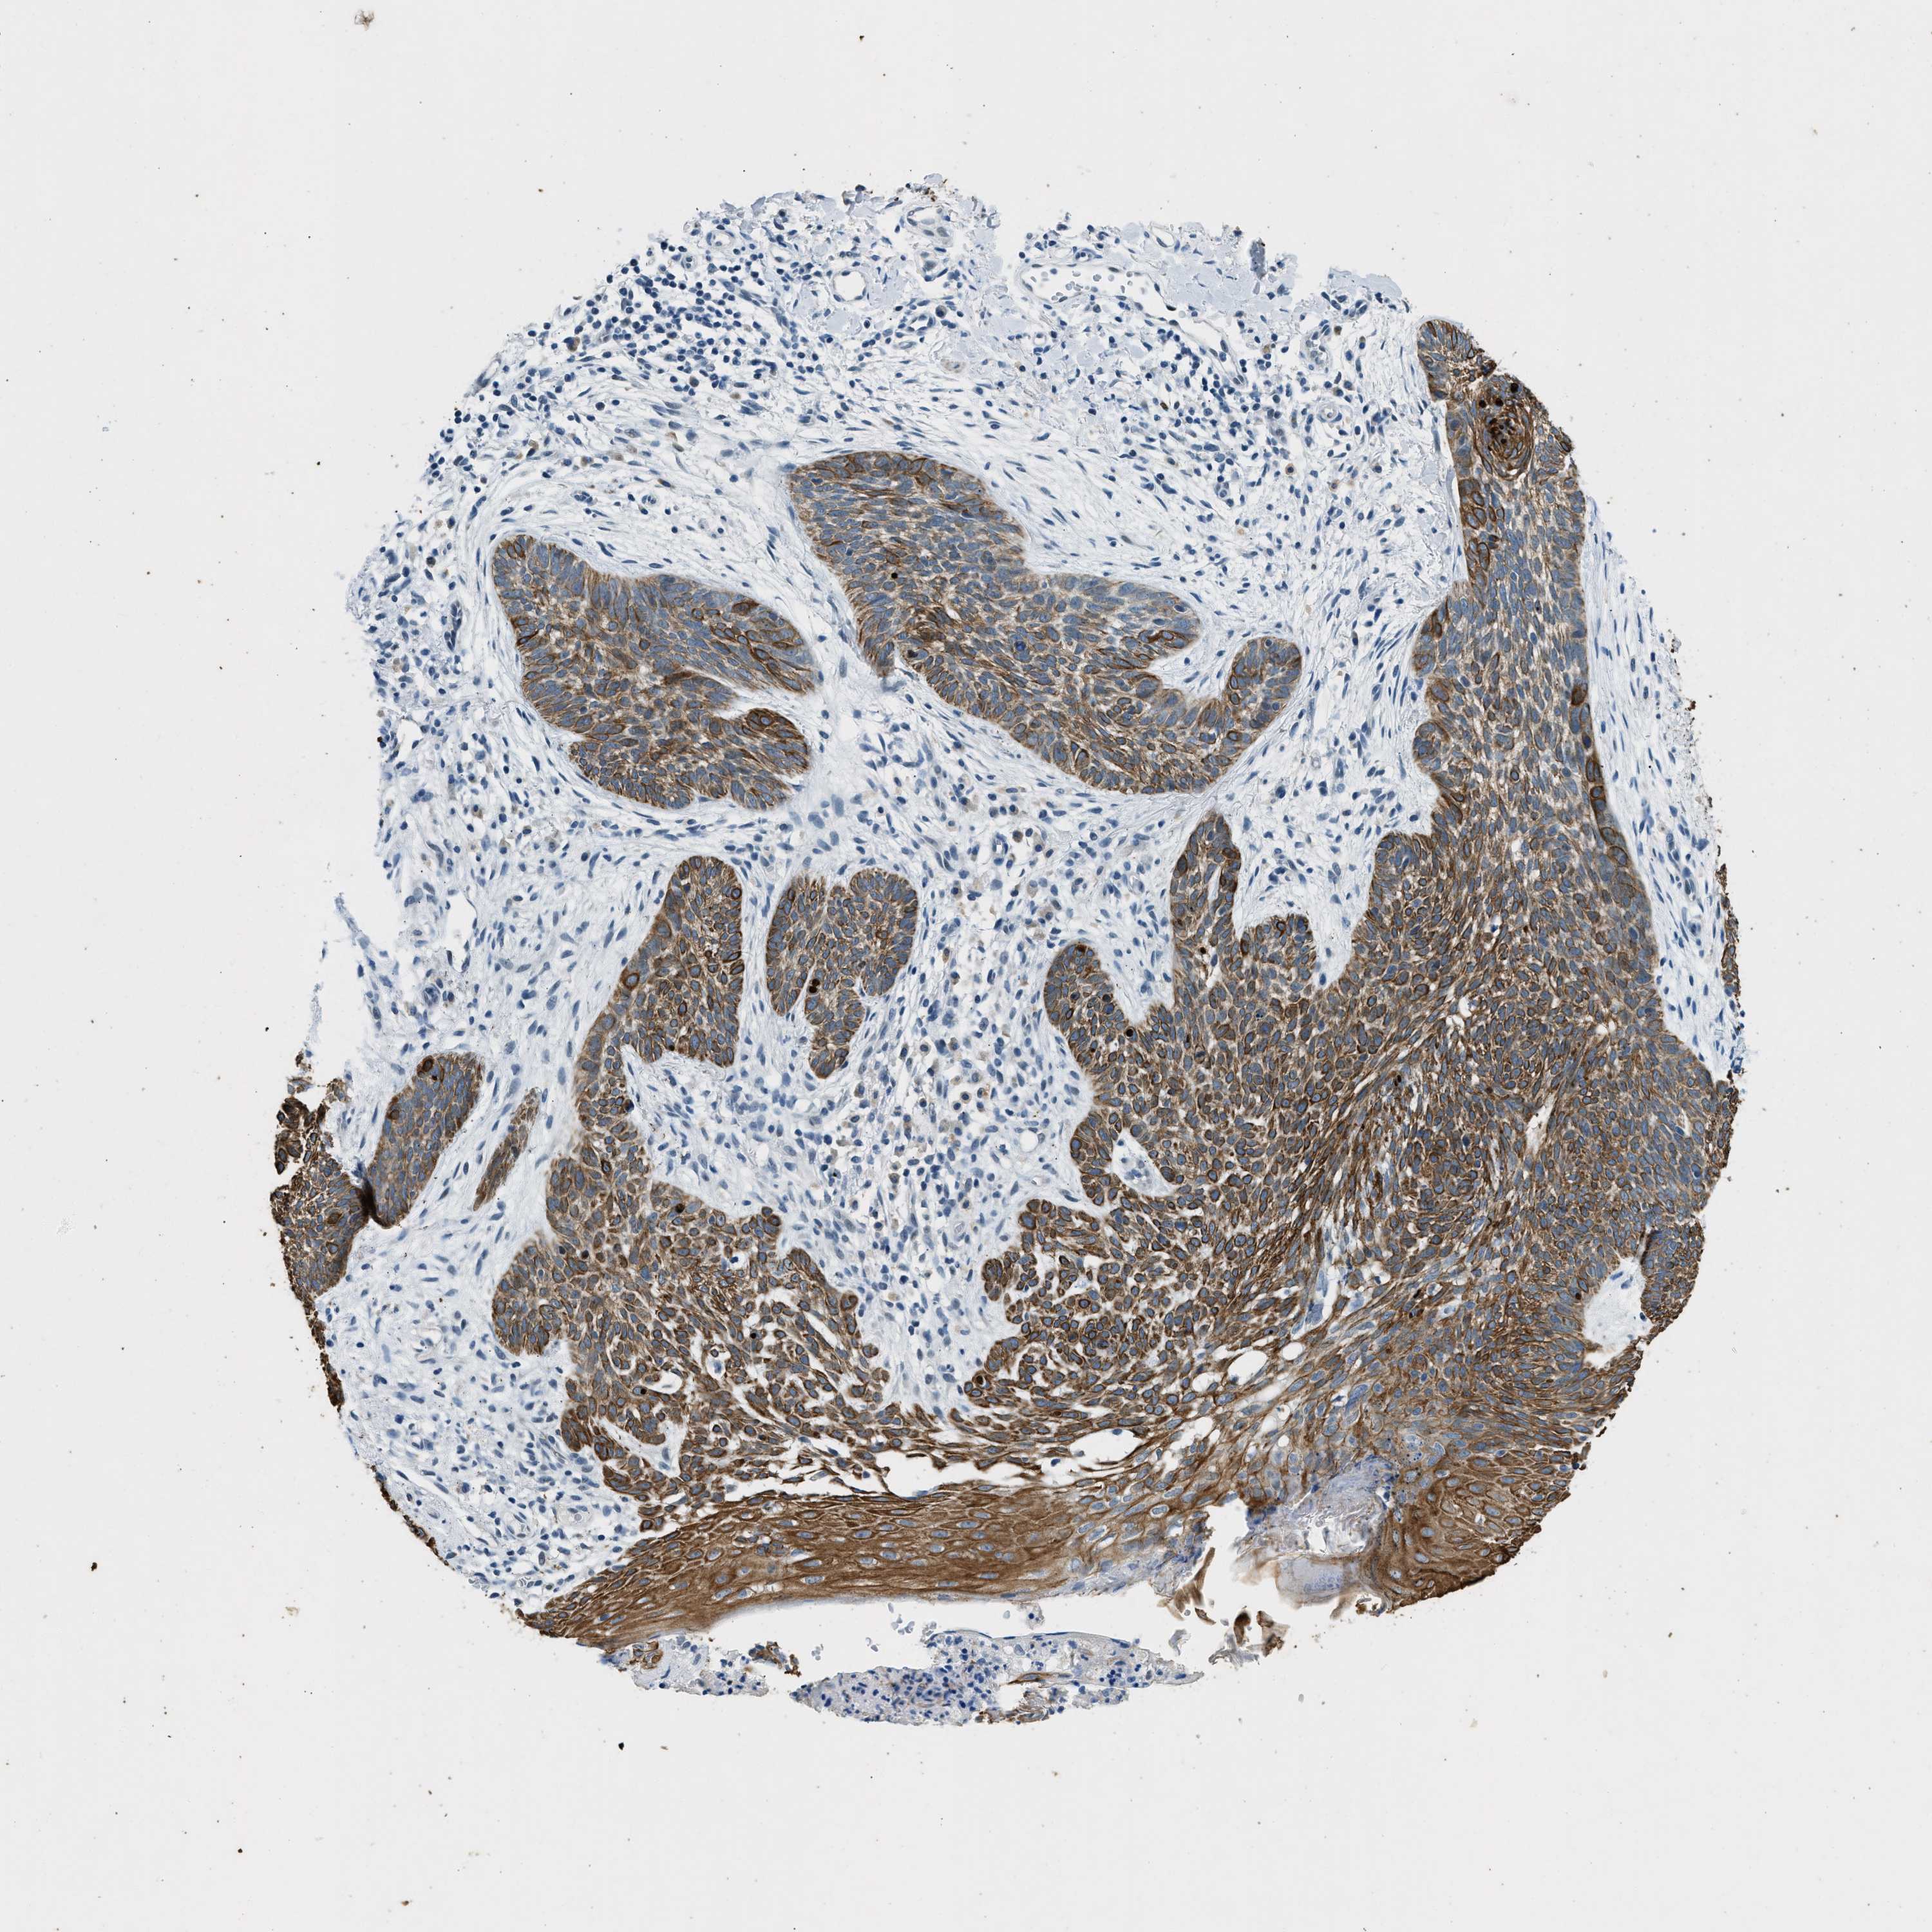

SKIN CANCER - Protein expressioni

A mouse-over function shows sample information and annotation data. Click on an image to view it in a full screen mode. Samples can be filtered based on level of antibody staining by selecting one or several of the following categories: high, medium, low and not detected. The assay and annotation is described here.

Antibody stainingi

Antibody staining in the annotated cell types in the current human tissue is reported as not detected, low, medium, or high, based on conventional immunohistochemistry profiling in selected tissues. This score is based on the combination of the staining intensity and fraction of stained cells.

Each image is clickable and will lead to virtual microscopy that enables deeper exploration of all samples and also displays staining intensity scores, fraction scores and subcellular localization as well as patient and tissue information for each sample.

Antibody HPA018195

Staining

High

Medium

Low

Not detected

Intensity

Strong

Moderate

Weak

Negative

Quantity

>75%

75%-25%

<25%

None

Location

Nuclear

Cytoplasmic/membranous

Cytoplasmic/membranous,nuclear

Squamous cell carcinoma, NOS